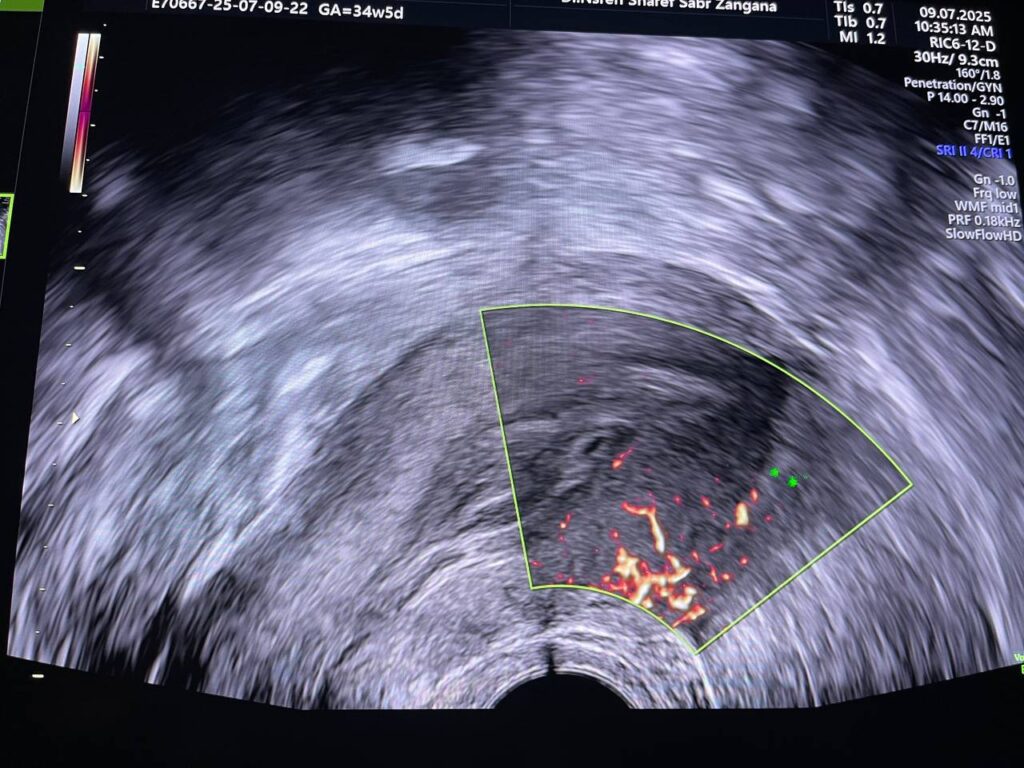

Bulky size, A/V uterus,  endometrial lining thickness 22mm, the cavity occupied by heterogenous avascular lesion 42x16mm , mostly blood clots? in addition to presence of few cysts with instinct  left anterior upper part of the endo myometrial junctional zone , in area size about 11.5x9mm, mostly remains of hydatiform wall  , please for further study   , no fibroid

This patient has high BHCG level , with History of H Mole on march 2025